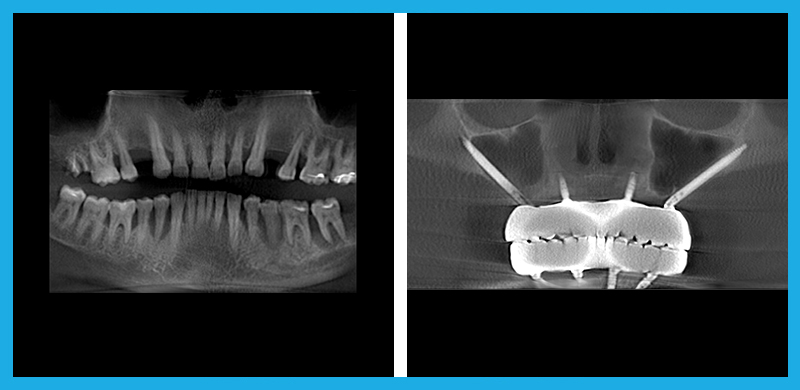

- Zygomatic and Pterygoid Implants: A Faster Solution: Traditional dental implant methods often require extensive bone grafting and a lengthy healing period, sometimes taking up to a year before final teeth are placed. Zygomatic and Pterygoid Implants bypass the need for bone grafts by anchoring the implants in the cheekbone and pterygoid plate, allowing for immediate loading of teeth. This not only shortens the treatment time dramatically but also provides a solution for patients who were previously told they weren’t candidates for implants due to severe bone loss.

Before and After

Zygomatic Implants